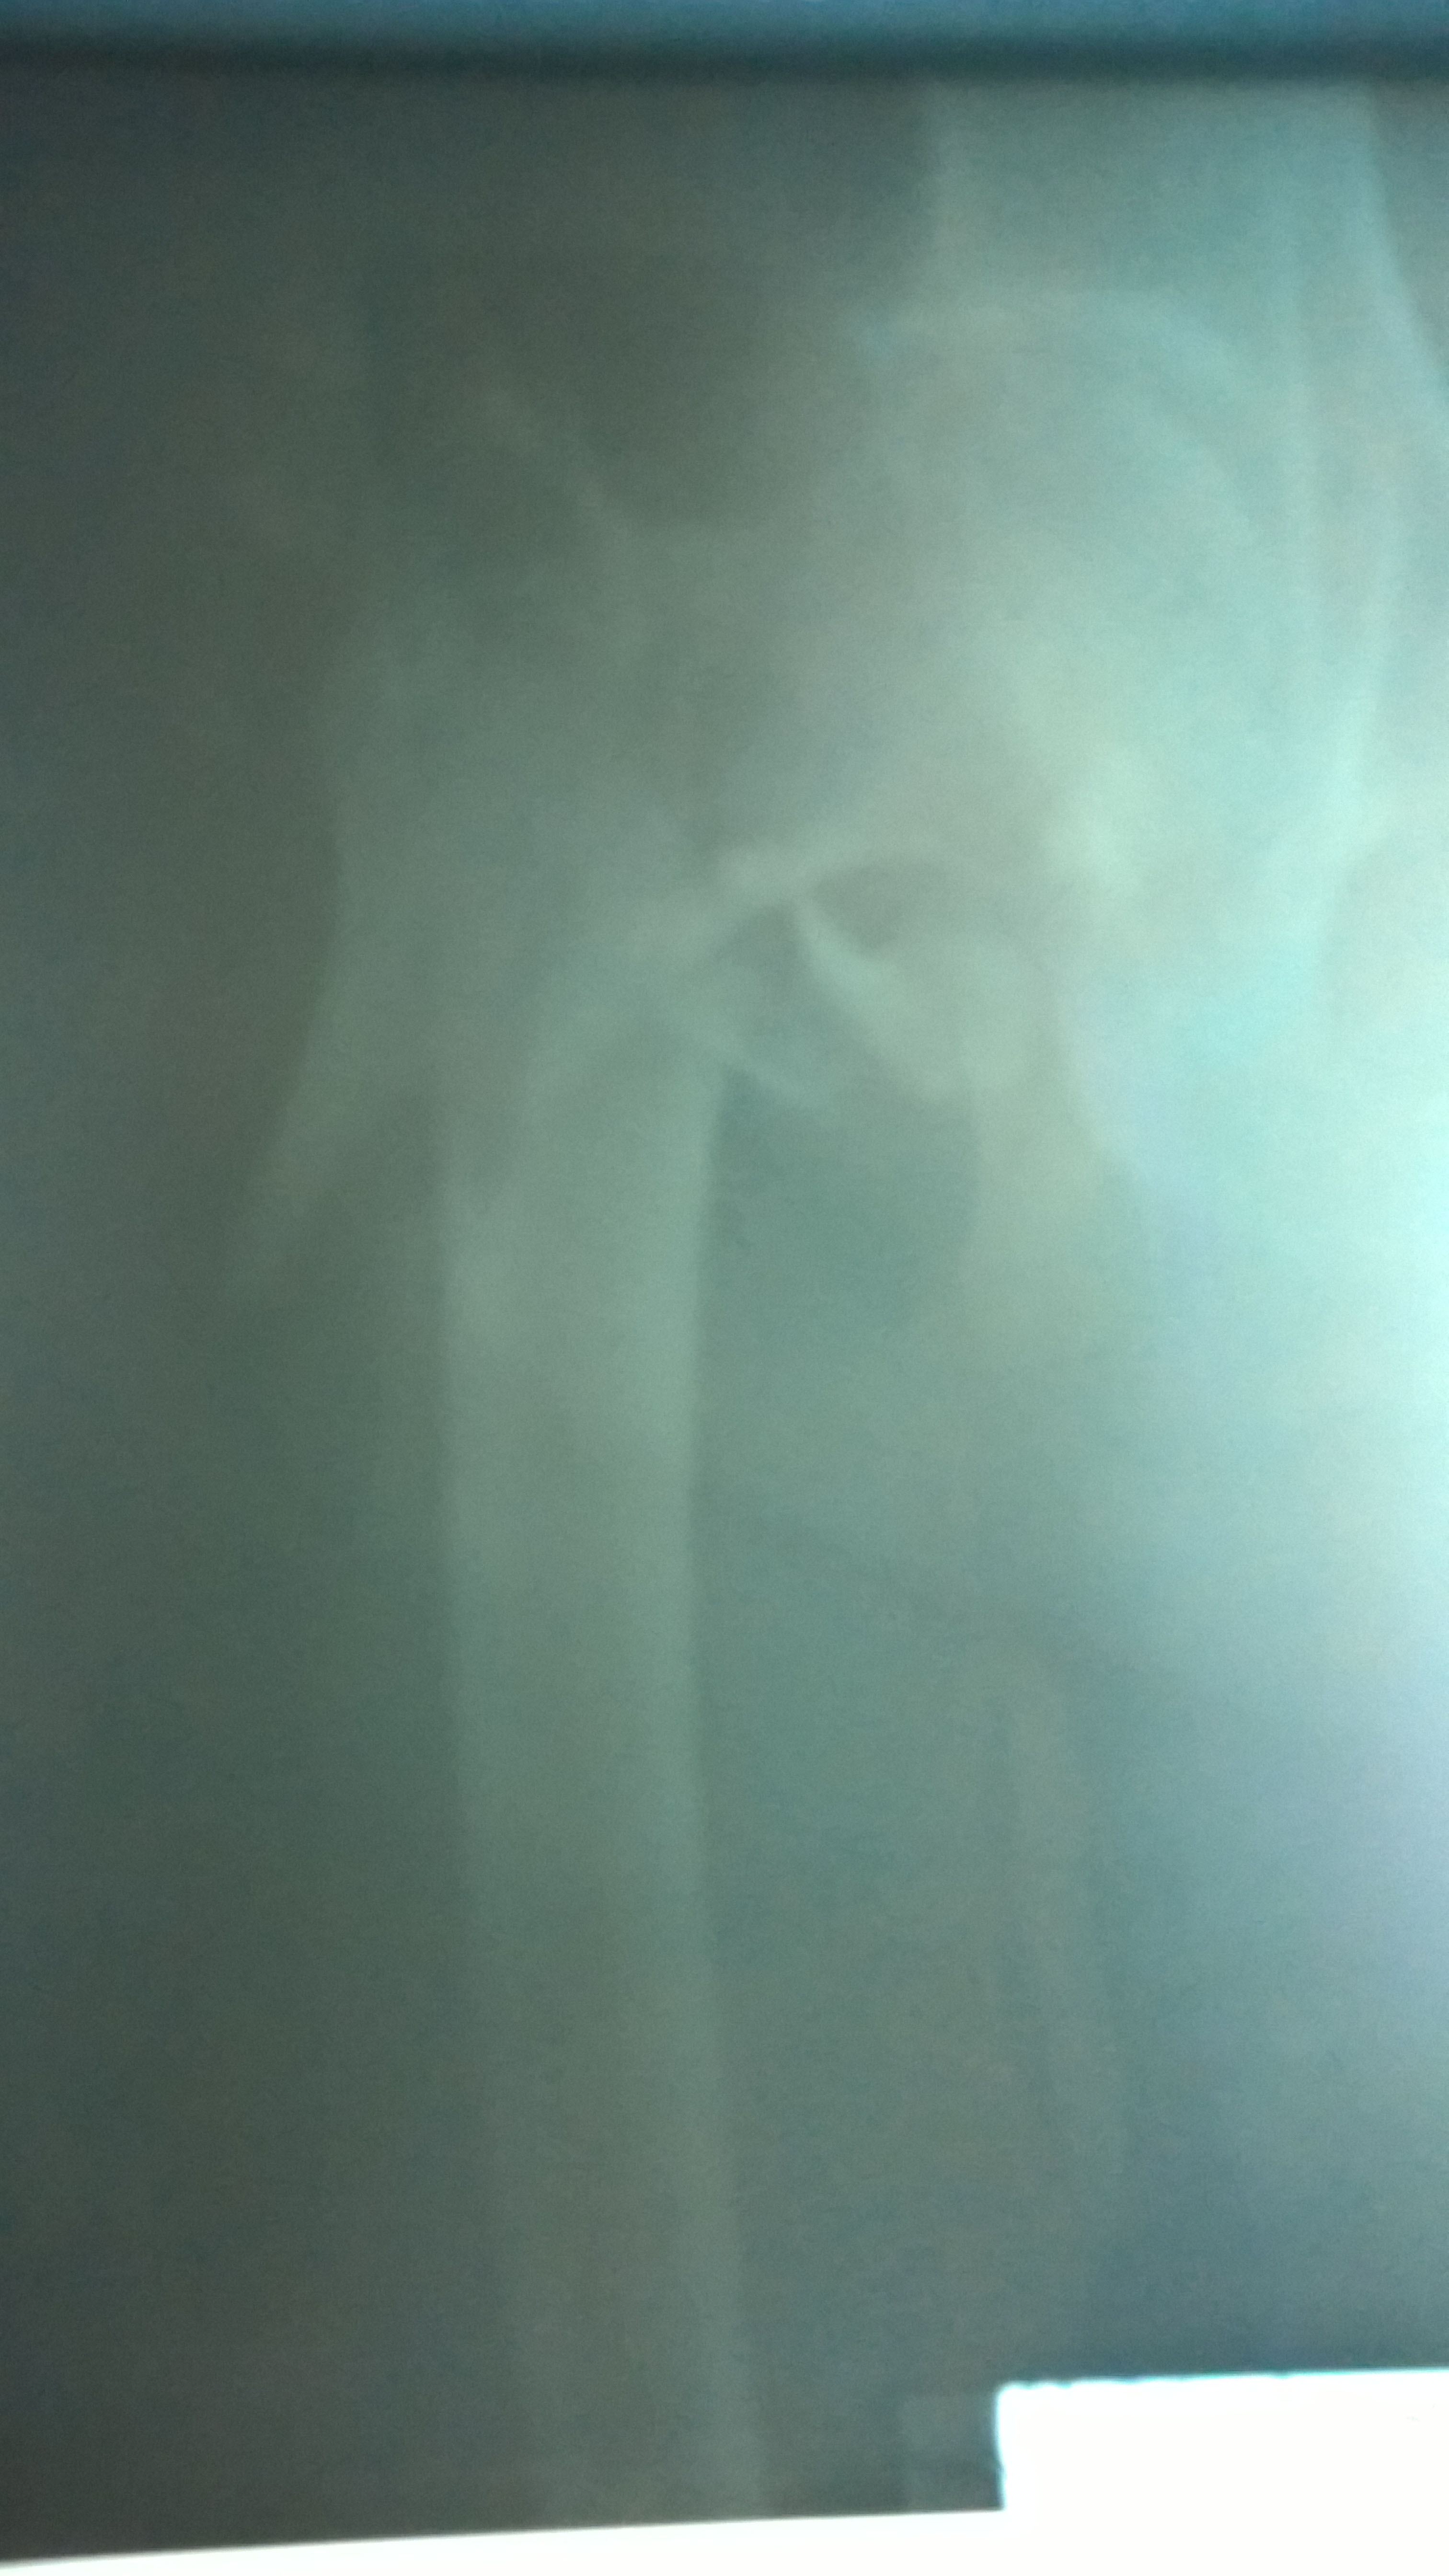

Современная методика лечения переломов бедренной кости - система PFNA (Proximal Femoral Nail Antirotation)